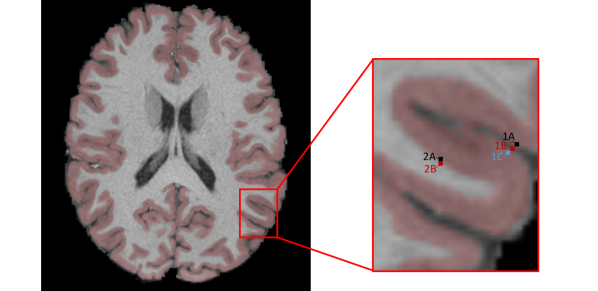

Cs-fMRI offers several advantages over volumetric fMRI, including better whole-brain visualization, dimension reduction, removal of extraneous tissue types, and improved alignment of cortical areas across subjects. However, perhaps the most important benefit of cs-fMRI is the greater neurobiological significance of distances in the cortical surface space. Nearby locations in cs-fMRI are close in terms of distance along the cortex, and therefore tend to exhibit similar patterns of neuronal activity, while in volumetric fMRI locations that are close in terms of Euclidean distance may be neurobiologically quite dissimilar, coming from different areas of the cortex or even different tissue classes as illustrated in Figure LABEL:fig:volumetric. Thus, cs-fMRI is more appropriate for use with methods that pool information across neighbors, such as spatial smoothing or Bayesian spatial models.

[Uncaptioned image]

These issues are symptomatic of some of the fundamental limitations of the classical GLM, described previously by Friston et al. (2002) and Friston and Penny (2003), among others. First, while it is well-known that the activation amplitude of one voxel depends on its neighbors, the classical GLM does not account for such dependence, since the model is estimated separately at every location. Second, while spatial smoothing of the fMRI data prior to model fitting can increase SNR and help satisfy the assumptions of RFT, when applied to volumetric fMRI data it may also combine signal from different tissue types and across discontiguous regions of the cortex (see Figure LABEL:fig:volumetric), contaminating the signal of interest and leading to inaccurate identification of truly active regions. Smoothing of cs-fMRI data is less problematic but also tends to blur boundaries between active and non-active areas. Furthermore, smoothed data may still fail to exhibit the Gaussian spatial autocorrelations required for RFT (Wald and Polimeni 2016). Smoothing also increases dependence between tests, complicating the problem of correcting for multiple comparisons.